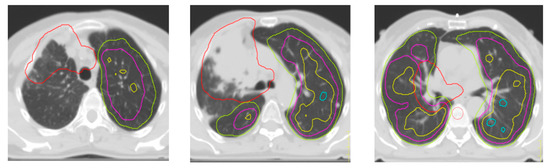

A Brief Report on the Role of SPECT/TC in the Optimization of Radiotherapy Treatment with Radical Intent for Unresectable Stage III NSCLC

2. Materials and Methods

3. Results